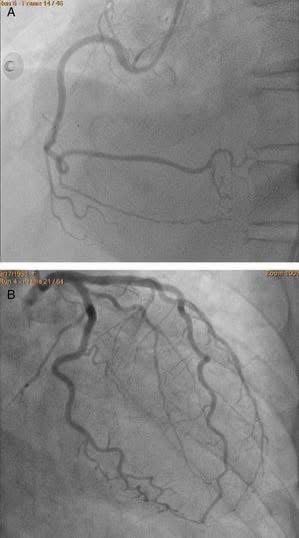

แต่พอฉีดสีไป ปรากฎเป็นภาพในรูปค่ะ

คือทุกเส้นปกติหมดเลยค่ะ

ไม่มีจุดตีบชัดเจน ที่อธิบายถึงอาการเลย